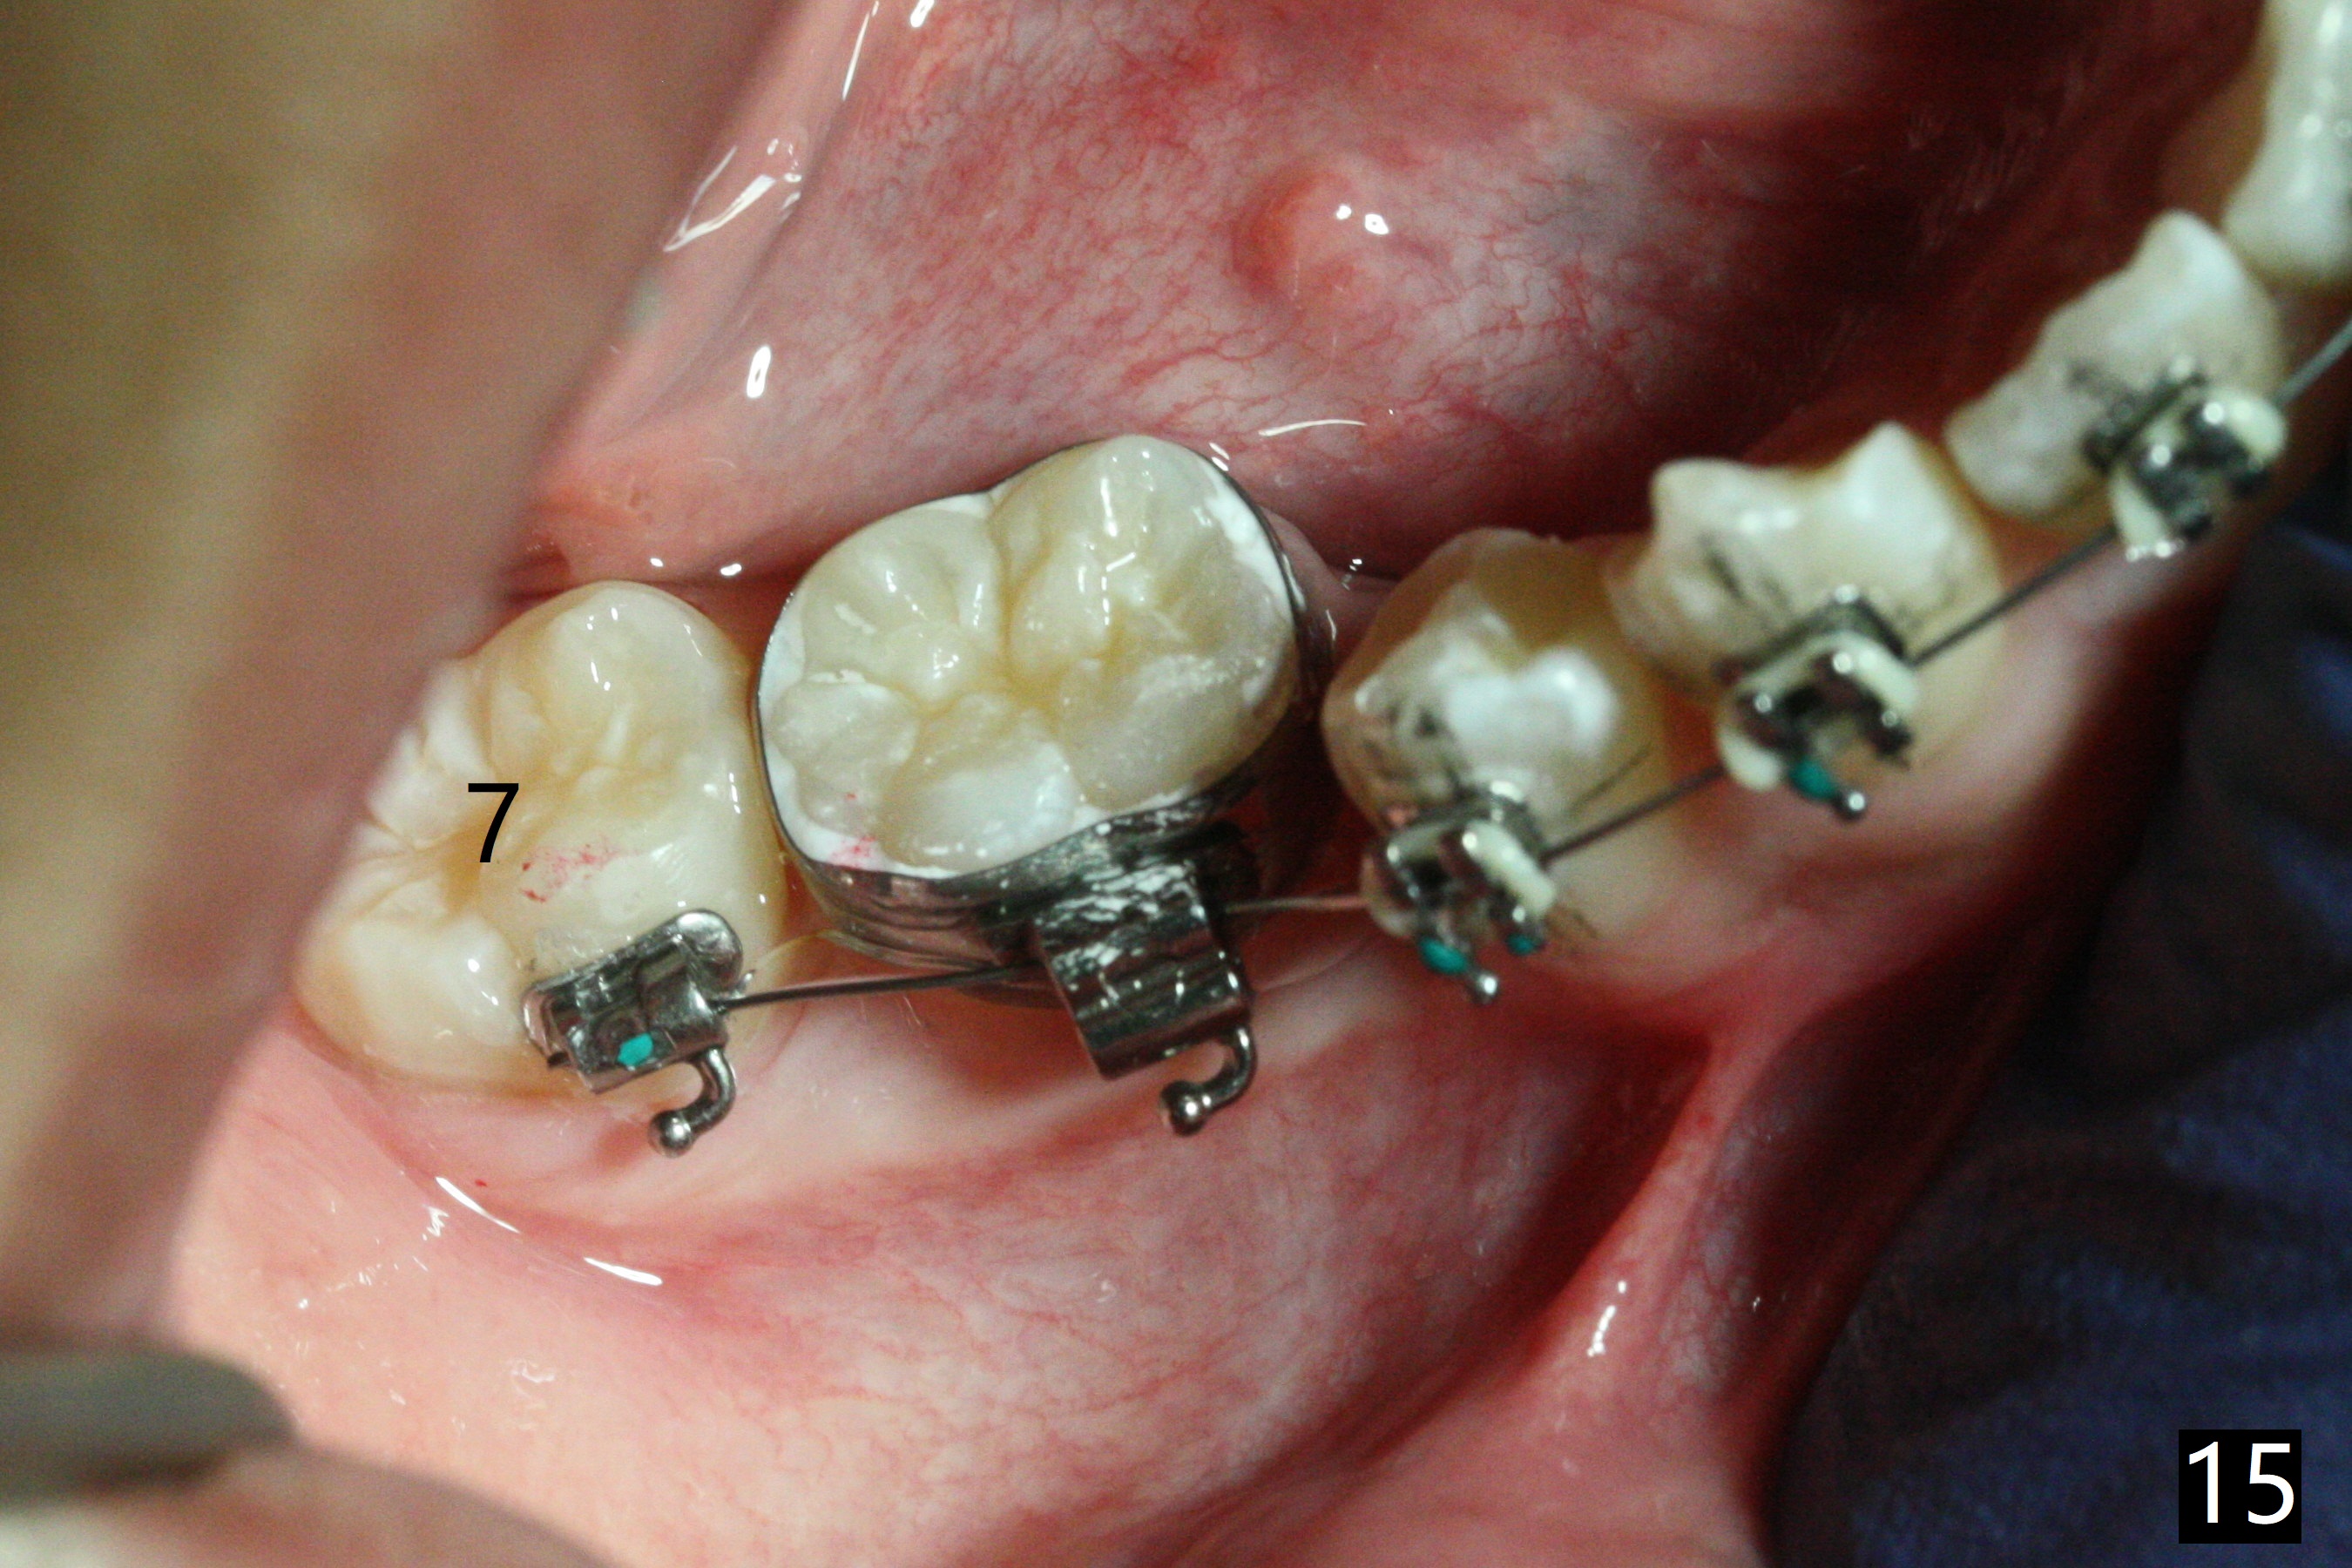

In fact, automatic shifting is striking.  For example, UR5 lingualization (Fig.12 arrow) makes it easy to insert 12 niti wire.  Distalization of the lower bicuspids and canine is more obvious (Fig.13,14 arrows) than the upper counterparts.  Because of incomplete eruption, it is difficult to band L7s; instead brackets are placed (Fig.15-17).  The purpose of LR one is to facilitate LR6 buccalization (Fig.15,16), whereas LL one to correct rotation of itself (Fig.17).